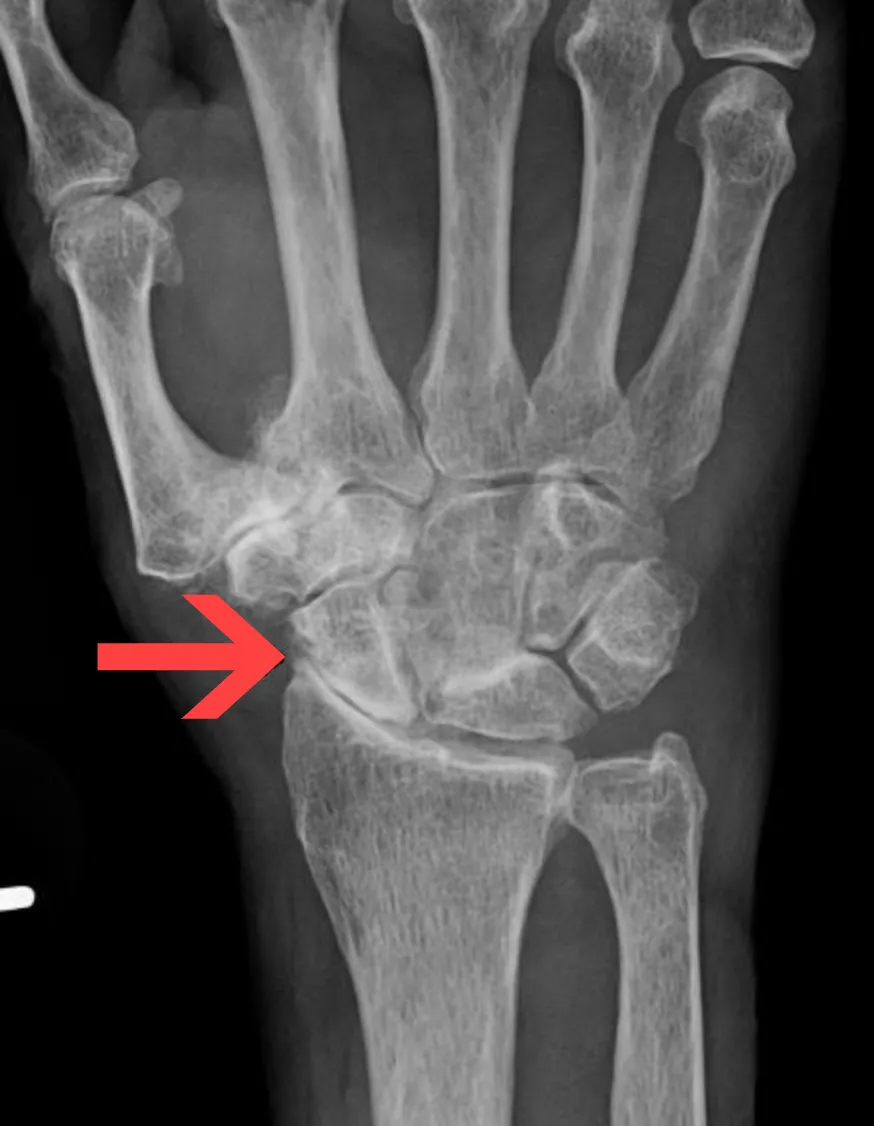

- Beeldvorming: met een röntgenfoto van de pols kan polsartrose bevestigd worden. Op de foto ziet men een versmalling van de gewrichtsruimte, botvergroeiingen (osteofyten) en soms standsafwijkingen van de polsbeentjes. In sommige gevallen wordt een CT-scan of MRI gemaakt om details van het gewricht en eventuele botschade beter in kaart te brengen.